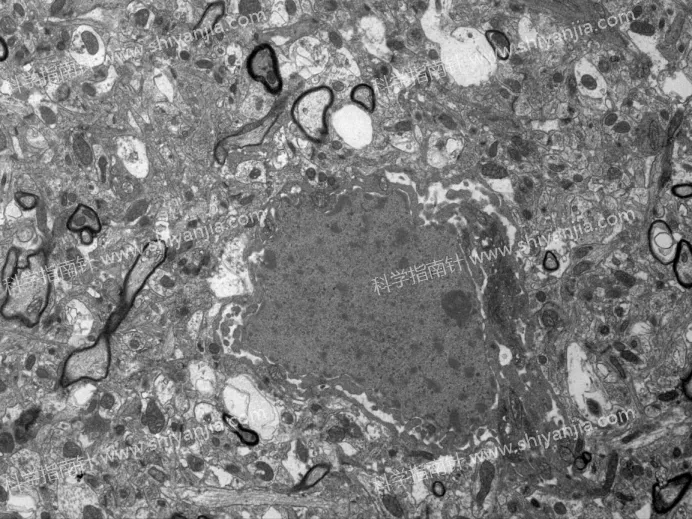

灌流组

2.2 分钟是黄金取材窗口:灌流组 2 分钟内取材,样本超微结构无显著退化,膜结构清晰、细胞器形态完好,是兼顾操作可行性与样本质量的最佳时间。

灌流组

灌流组